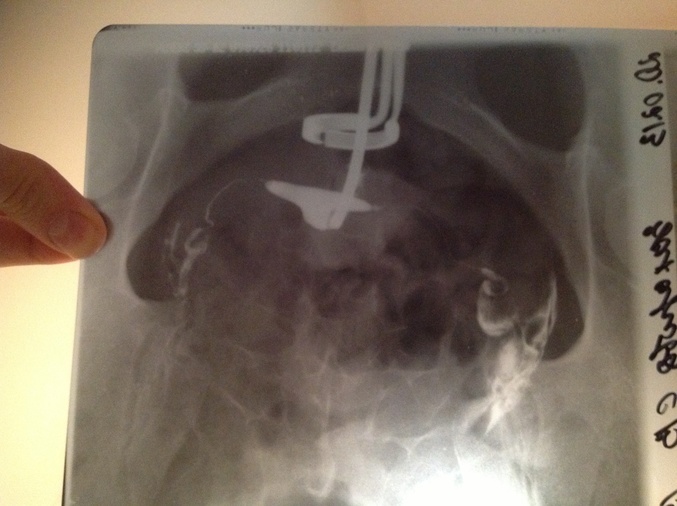

Я сделала ГСГ. Врач очень хороший, квалифицированный, только хорошие отзывы о нем слышала и читала. Сказал, что трубы у меня проходимы, все ОК, отправил беременеть. Я счастливая целую неделю на крыльях летала!

А сегодня ходила к своему гинекологу. Она совершенно по-другому интерпретировала результаты. Показала мне по снимку, что да, трубы проходимы, но жидкость из них вылилесь не вниз, как положено, а куда-то вверх пошла! Т.е. трубы повернуты вверх!! Таким образом, семенная жидкость никаким образом не сможет попасть в яичники, и, соответственно, беременность невозможна!!

Типа, могло (и было) воспаление, из-за него образрвались спайки в трубах и они загнулсь вверх

Такое вообще возможно???? Предлагает сделать лапару, чтобы посмотреть поподробней. ПОзвала для консультации другого врача из отделения. Тот согласился с ней. Явот не понимаю, такой бред вообще мог случится??? МОгли ли трубы "уползти" вверх? И какие-такие спайки, если трубы проходимы??? Так не хочется делать операцию!!! Девочки, пожалуйста, помогите советом!!